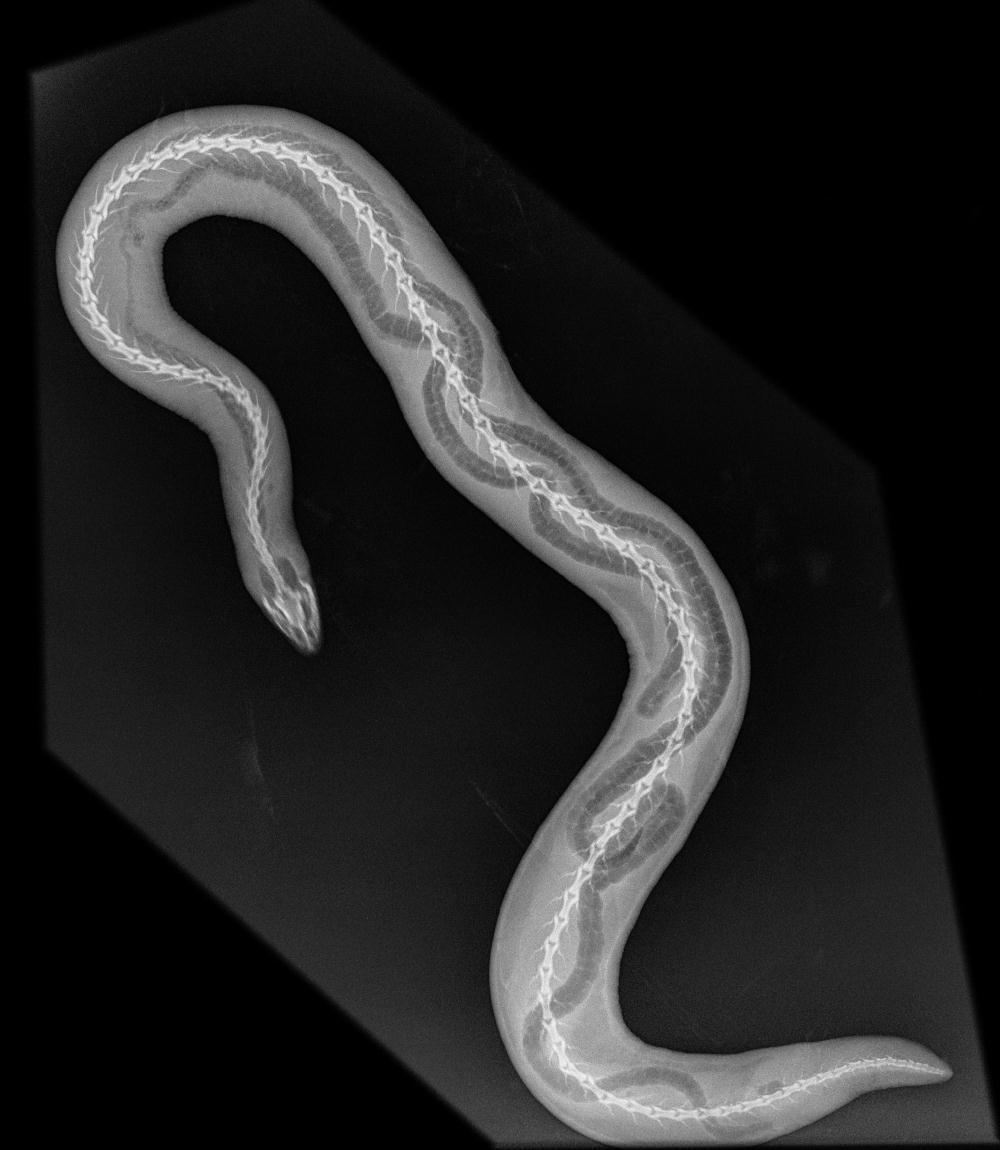

RÖNTGEN KÄÄRME.jpg Jaa Sulje Tämän kuvan tekstivastine: (tyhjä tekstivastine) RÖNTGEN KÄÄRME.jpg 93.6 kt